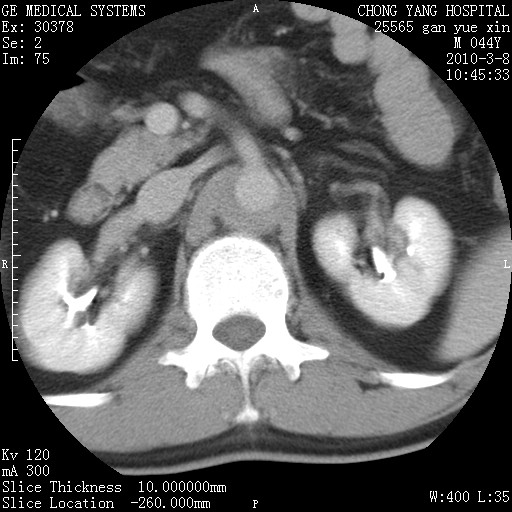

标题: CT24940:主动脉增强,典型病例。 [打印本页]

标题: CT24940:主动脉增强,典型病例。

夹层动脉瘤。

动脉夹层

主动脉夹层。

动脉夹层的分型:

⒈debakey分型:根据主动脉夹层累及部位,分为三型:ⅰ型:原发破口位于升主动脉或主动脉弓部,夹层累及升主动脉、主动脉弓部、胸主动脉、腹主动脉大部或全部,少数可累及髂动脉。ⅱ型:原发破口位于升主动脉,夹层累及升主动脉,少数可累及部分主动脉弓。ⅲ型:原发破口位于左锁骨下动脉开口远端,根据夹层累及范围又分为ⅲa,ⅲb。ⅲa型:夹层累及胸主动脉。ⅲb型:夹层累及升主动脉、腹主动脉大部或全部。少数可累及髂动脉。

⒉stanford分型:a型:夹层累及升主动脉,无论远端范围如何。b型:夹层累及左锁骨下动脉开口以远的降主动脉。

夹层动脉瘤,少量胸水

夹层动脉瘤;左侧少量胸腔积液。